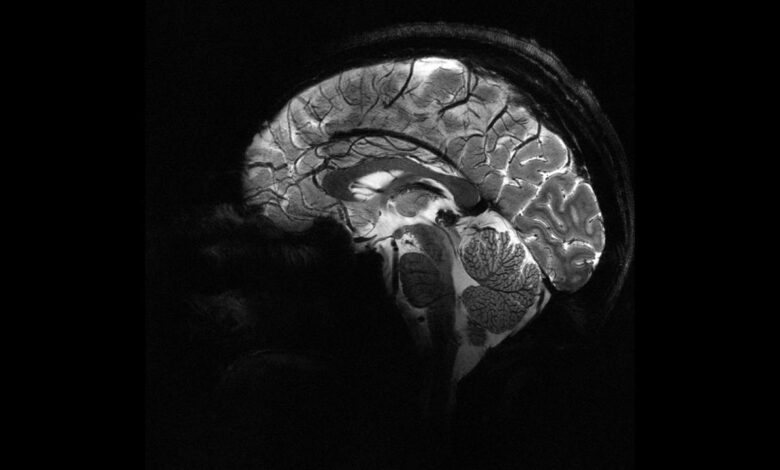

Deney sırasında beynin ön ve arka kısımlarında yer alan frontal ve paryetal bölgelere elektrik akımı uygulandı. Bu iki bölge aynı anda uyarıldığında, katılımcıların daha fazla para paylaştığı gözlemlendi.

Bu çalışma, katılımcıların para paylaşma oyunu sırasında beyin aktivitelerinin izlendiği önceki bir araştırmaya dayanıyor. Önceki çalışmada, daha fazla para paylaşıldığında beynin karar verme ve empati bölgelerinin aynı frekansta “iletişim kurduğu” tespit edilmişti. Yeni deneyle birlikte, dışarıdan müdahale ile bu bölgeler arasındaki iletişimin tetiklenebileceği ve insanların daha özverili kararlara yönlendirilebileceği kanıtlanmış oldu.

Araştırma ekibinden Dr. Jie Hu, çalışmanın en yeni yanının neden-sonuç ilişkisini ortaya koyması olduğunu söyledi. Hu, hedeflenmiş ve cerrahi müdahale gerektirmeyen bir stimülasyonla belirli bir beyin ağındaki iletişimin değiştirilmesinin, insanların kendi çıkarları ile başkalarının çıkarları arasındaki dengeyi nasıl kurduklarını doğrudan etkilediğini vurguladı.